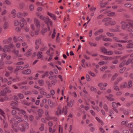

To deal with some of the aforementioned issues, we introduce a new approach for simultaneous H&E stain normalization and augmentation based on the multimarginal Wasserstein barycenter approach. Specifically, the novelty of the paper lies in first introducing the traditional Wasserstein barycenter approach for stain normalization/augmentation (Figure 1), and then introducing the multimarginal version [1, 9] to overcome the limitations of the traditional approach in this context (Figure 2). Note that the traditional Wasserstein barycenter (1 source and 1 reference), although widely employed in computer vision, to the best of our knowledge has never been used for stain normalization/augmentation and the more general multimarginal Wasserstein barycenter (1 source and multiple references) has hardly ever been used in computer vision or medical imaging communities. For more accurate stain normalization, the multimarginal version allows one to incorporate additional distributions by utilizing one or more intermediate reference images (Figure 2). The resultant interpolations span a broad spectrum of stain variations allowing for simultaneous stain normalization and augmentation.

In the present work, we also employ one source distribution and either or reference distributions (). For in (6), i.e., two or more references, we use the term “multimarginal OMT,” to emphasize the fact that we are considering more than two measures. For the application to images, one can always normalize to make sure that the total mass (intensity) is 1.

Further in the examples below (see Section 4), we choose , . Let denote the optimal solution of (6), that is, the barycenter. Notice that taking and as the marginals, we also find the optimal transport map We also set the parameter , which is the number of intermediate reference images. Thus, refers to the usual Wasserstein barycenter computed with respected to a reference and a source, with no intermediate reference images.